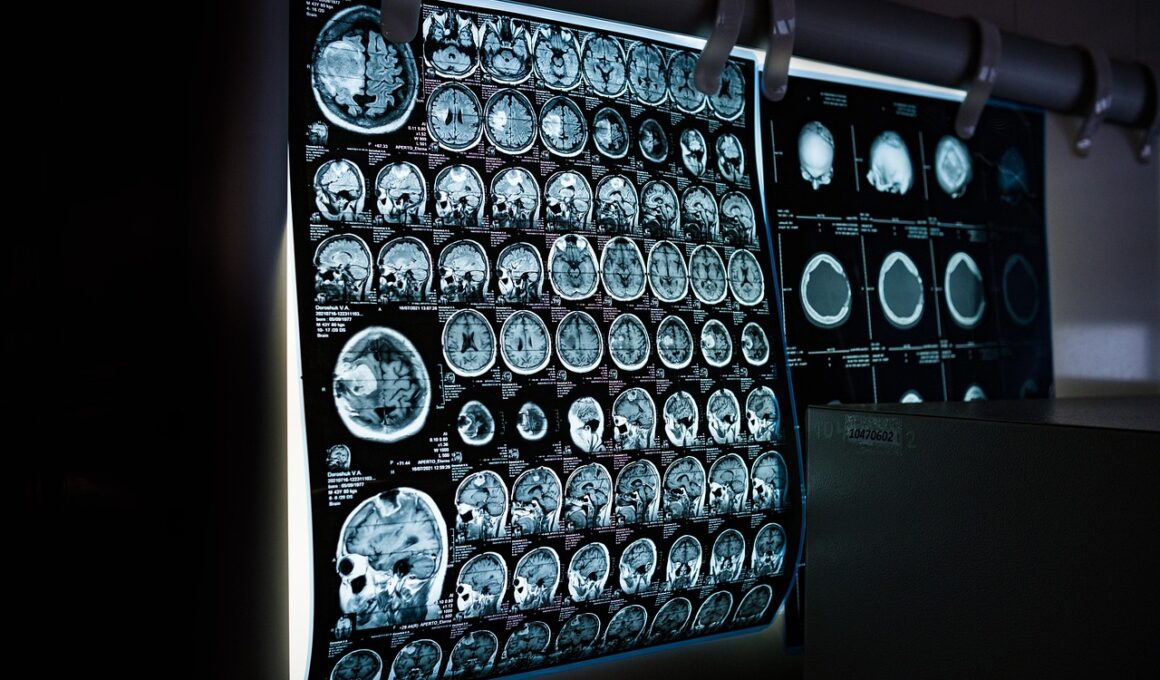

Effective imaging is essential when assessing sports injuries, as it plays a vital role in understanding the extent of damage and the healing process. Imaging modalities like MRI, CT scans, and ultrasounds help to visualize soft tissues, bones, and joints. These techniques assist sports medicine professionals in determining the diagnosis and formulating a rehabilitation plan for athletes. MRI is particularly valuable due to its ability to provide detailed images without exposing patients to ionizing radiation. Furthermore, advanced imaging techniques, such as functional MRI, allow for even deeper insight into recovery periods and movement-related injuries. CT scans, on the other hand, are invaluable for correlating complex fractures usually found in high-impact sports; they provide enhanced detail and clarity. Ultrasound is minimally invasive and helps in guiding therapeutic interventions while monitoring healing progress. By utilizing these imaging tools, sports medicine practitioners gain a competitive advantage in diagnosing and treating injuries, ensuring a comprehensive understanding of the athlete’s current condition. Thus, incorporating imaging techniques into the recovery protocol is essential for a successful return to sport in a safe manner.

Cross-sectional imaging techniques, such as MRI and CT scans, have advanced significantly, revolutionizing how sports injuries are assessed and treated. Innovations in imaging technology allow for quicker and more detailed examinations, leading to faster diagnoses. This rapid turnaround time means that athletes can begin treatment sooner, ultimately shortening their recovery periods. Furthermore, the high-quality images obtained through modern modalities allow for the detection of subtle injuries that may have been previously overlooked. Early detection can be critical in avoiding chronic issues that may affect an athlete’s performance later in their career. The integration of advanced imaging technologies has also fostered collaboration among various specialties within sports medicine, enhancing interdisciplinary care. For example, radiologists work closely with orthopedic surgeons and physiotherapists, ensuring that everyone involved has a comprehensive understanding of the injury. Continuous training and education on these imaging systems ensure that sports medicine professionals remain up-to-date with best practices, enhancing the overall care provided to athletes. This joint effort underlines the significant role that modern imaging technologies play in promoting a tailored and focused rehabilitation strategy for each athlete.